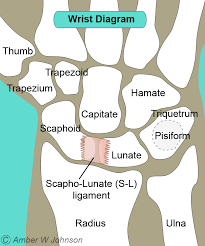

对于舟骨骨折,我们是否还应该固定拇指,还是只固定腕部石膏就同样有效?

文章:Harper, KJ、Rees, Y.、Tan, NX、Li, H.、Fonseca, EA、Quach, PG、Lee, GS、Brayshaw, JR 和 McGarry, S. (2025)。 ...